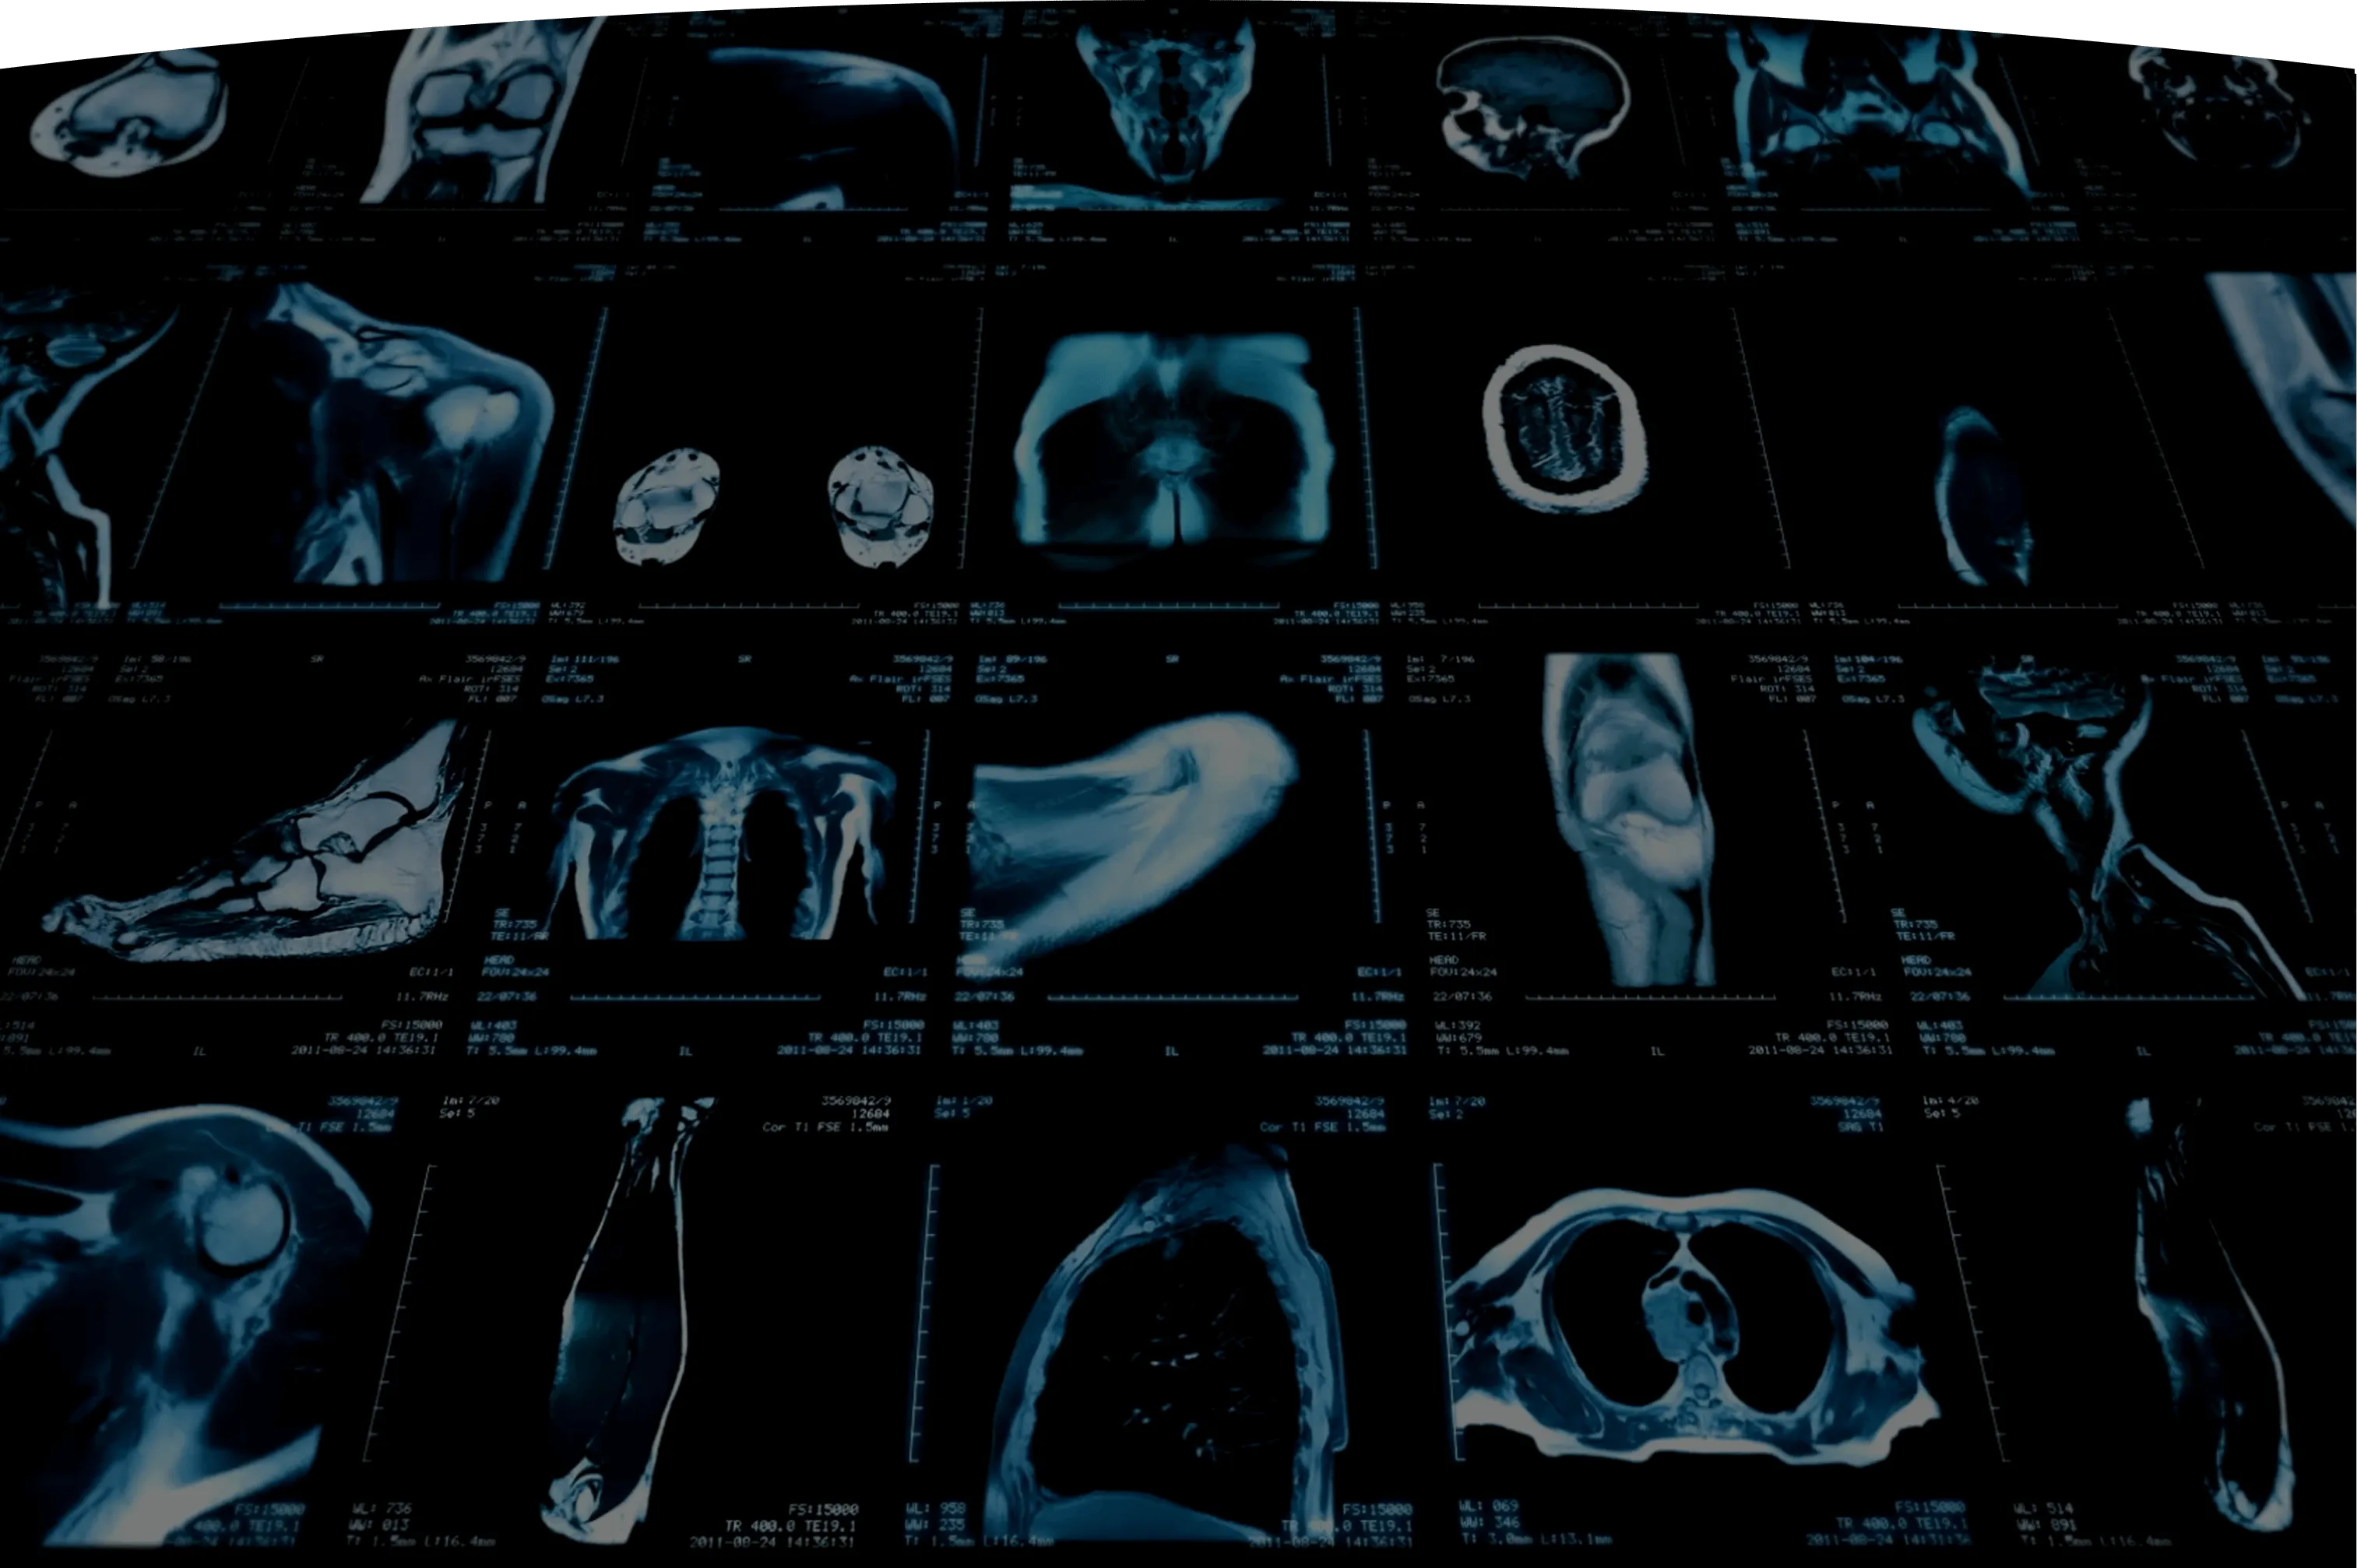

Designed for what’s next in healthcare

A fully standardized system from imaging technology to radiology interpretation – delivering insights you can track year over year.

Integrated technology, guided by the Prenuvo Medical Group*

Every clinic, scanner, and radiologist operates within a standardized system. Our exclusively-affiliated board-certified radiologists interpret each scan with AI support to enhance accuracy and consistency.

*Our exclusively-affiliated group partners that are providing medical services to Prenuvo.